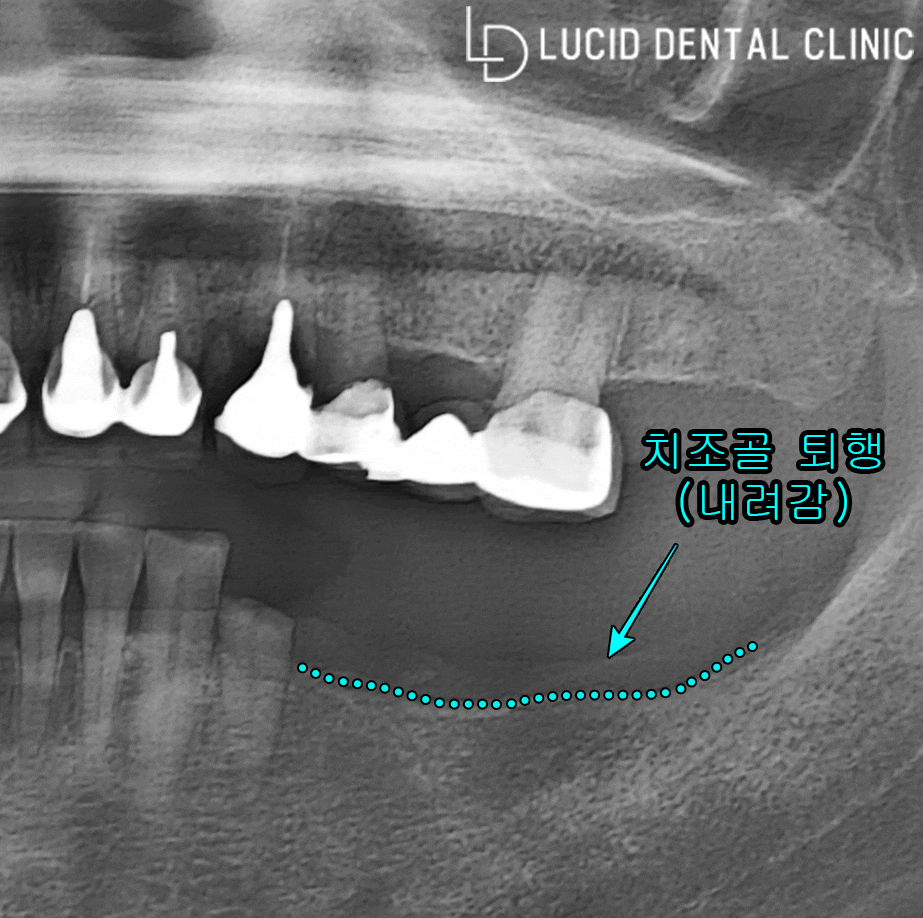

곧장 파노라마 엑스레이 사진을 통해

환자의 주소를 중점으로 진단했습니다.

그 결과, 위와 같이 발치 후 비어있는

아래턱 어금니와 함께 위턱 치아 주변으로

거뭇한 염증이 나타난 걸 알아낼 수 있었습니다.

위, 아래 현황이 지금 이러니

제대로 된 교합은 물론 불편이

심해질 수밖에 없었던 것이죠...